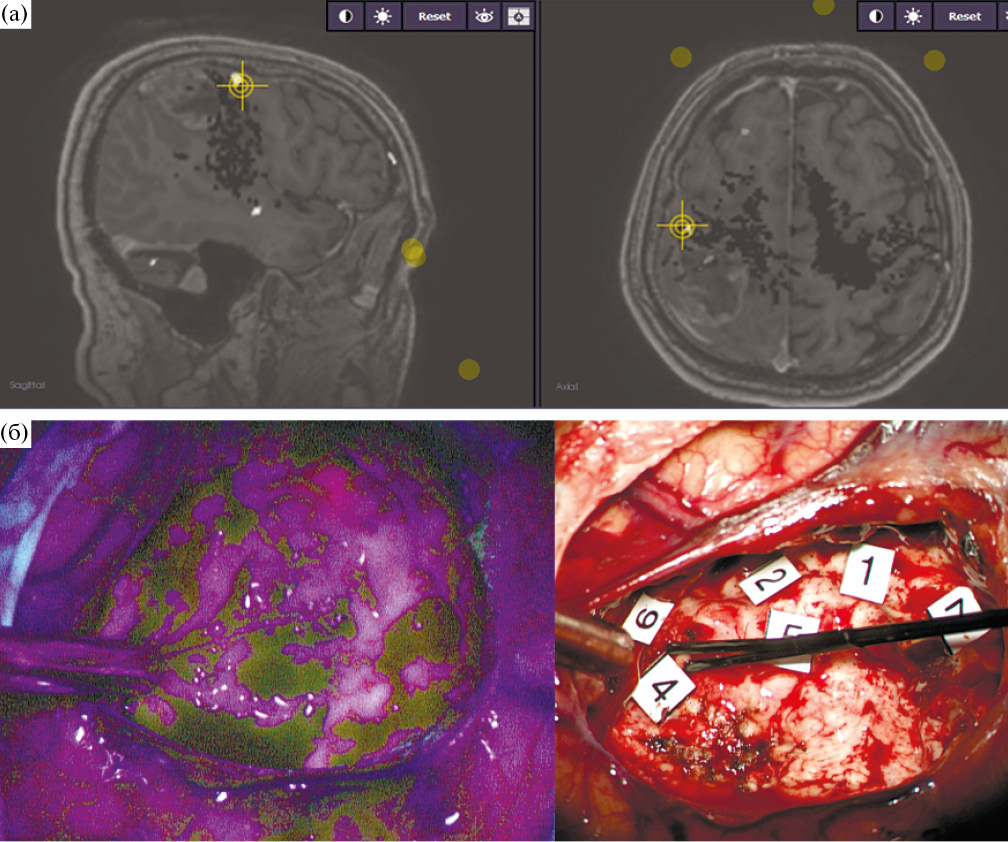

Интраоперационная оценка радикальности удаления также значимо не отличалась в контрольной и основной группах (р = 0.812). В контрольной группе хирург предполагал наличие остатков опухолевой ткани в 45.5% случаев, в основной – в 39.2%. При этом у 12 пациентов основной группы (19%), по данным протоколов операции, данные ФМ были использованы как основание для расширения резекции. Основными причинами остановки резекции были распространенный характер опухоли с инфильтрацией глубинных структур головного мозга, переходом на противоположное полушарие и фиксация к магистральным кровеносным сосудам (12 пациентов: 7 – в основной группе и 6 – в контрольной) и, что более принципиально в данной выборке, появление моторных ответов при ПКС и ПСС (16 пациентов: 15 – в основной группе и 1 – в контрольной) и снижение ТК МВП (2 пациента из основной группы и 1 – из контрольной). Таким образом, в основной группе в большем количестве случаев резекция была ограничена ввиду объективных лимитирующих причин. Интересным фактом является то, что у трех пациентов из основной группы положительные моторные ответы были получены при стимуляции в участках с интенсивной флуоресценцией при пороговой силе тока в 5 мА, что в очередной раз подтверждает инфильтративный характер роста глиальных опухолей и возможность включения в строму опухоли нормально функционирующей мозговой ткани (рис. 2).

Рис. 2. (а) – интраоперационная фотография ложа удаленной опухоли у пациента с глиобластомой левой лобной доли в «белом свете». Визуально определяется неизмененное мозговое вещество, при прямой субкортикальной биполярной и монополярной стимуляции с пороговой силой тока 5 мА в этой области получены моторные ответы с языка. (б) – интраоперационноая фотография той же области. В зоне стимуляции определяется яркая розовая флуоресценция, что свидетельствует о наличии опухолевой ткани. У данного пациента резекция была остановлена.

Fig. 2. There are motor responses by direct bipolar with a threshold current of 5 mA stimulation in the bright pink fluorescence area.

Данному пациенту проводилась поточечная сравнительная монои биполярная стимуляции, в ходе которых получено 6 точек с моторными ответами в ложе удаленной опухоли (рис. 5). Параметры стимуляции в данных точках следующие: для монополярной стимуляции сила тока составила в т. 1–3–4 мА (кисть), т. 7–5–6 мА (кисть), т. 6–5 мА (кисть), т. 9–3–4 мА (плечо), т. 8–4 мА (кисть); для биполярной – в т. 7–6.5 мА (кисть), т. 6–14 мА (кисть), т. 2–3–4 мА (плечо), т. 5–2–5 мА (кисть). Таким образом, ответы были получены во всех точках как при моно-, так и при биполярной стимуляциях, вовлекаемые в ответ мышцы также были идентичны. Пороговая сила тока составила 3 мА для монополярной стимуляции и 2.5 мА – для биполярной. Опухоль удалена в пределах макроскопически неизмененной мозговой ткани. В режиме флуоресценции наблюдалось остаточное розовое свечение, соответствующее по локализации т. 1, где были получены положительные моторные ответы от кисти на низком пороговом токе (3 мА). Этот участок был оставлен, несмотря на наличие флуоресценции, с целью снижения риска развития моторного дефицита в послеоперационном периоде.

Рис. 5. (а) – интраоперационная фотография монитора навигационной системы FIAGON. Маркером отмечена точка, при стимуляции которой получены положительные моторные ответы с мышц кисти. Данная точка соответствует в данном случае моторной коре. (б) – интраоперационная фотография ложа удаленной опухоли в режиме флуоресценции и в «белом свете». Маркерами отмечены точки, при субкортикальной стимуляции которых получены положительные моторные ответы. Видно, что в «белом свете» ложе опухоли представлено нормальной мозговой тканью. В режиме флуоресценции отмечается фокальное розовое свечение (соответствующее т. 1). Данный участок оставлен во избежание нарастания моторного дефицита.

Fig. 5. Intraoperative photos. The tumor resection cavity with markers of stimulation points (motor response) and residual focus of the fluorescence.